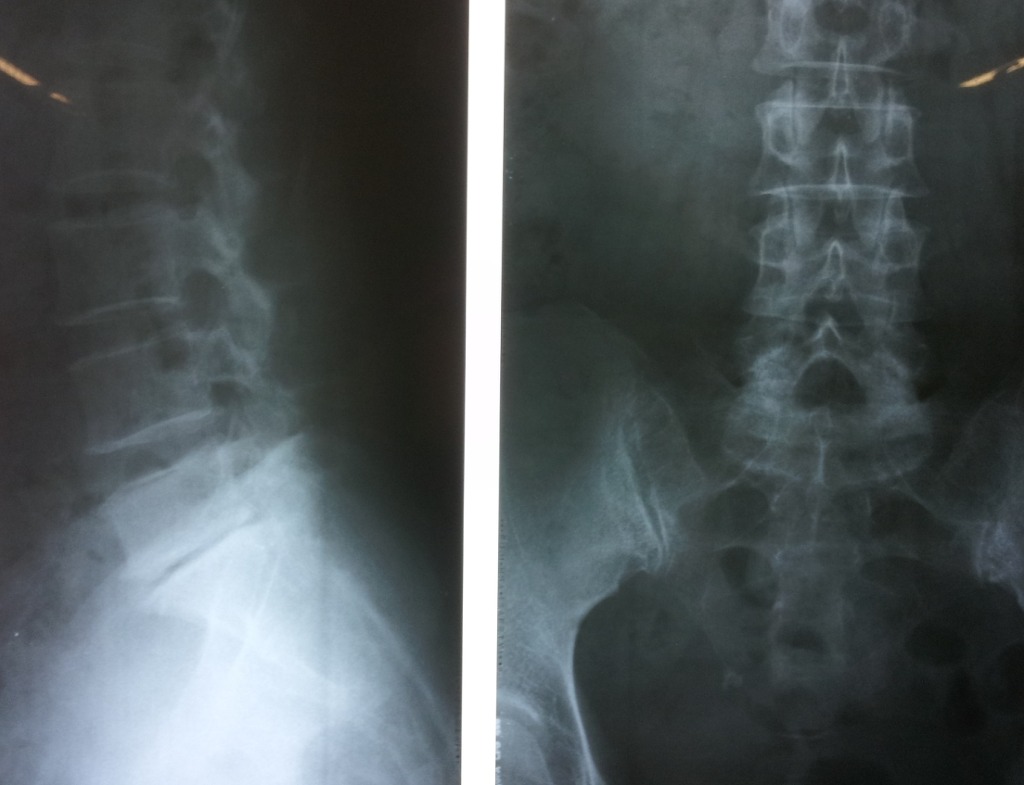

l-spine ap and lat : l5-s1 disc space narrowing

lt knee caption(patella) lateral subluxation - static 평가